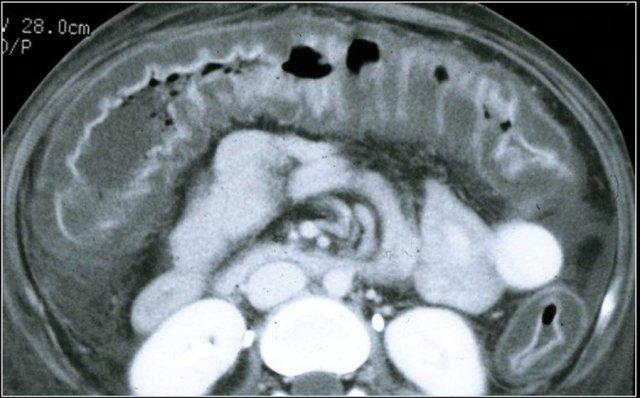

Đây là hình ảnh của một bệnh nhân mắc PMC.

Có hình ảnh cổ trướng và thành ruột ngấm thuốc mạnh kèm phù nề lớp dưới niêm mạc và phù nề mạc treo đại tràng.

Đoạn ruột giãn ở hố chậu phải thực chất là đại tràng sigma dư thừa.

Chẩn đoán được xác lập bằng cách xét nghiệm phát hiện độc tố của C. difficile trong phân hoặc phát hiện chính vi khuẩn C. difficile.

Các dấu hiệu trên CT bao gồm:

- Dày thành ruột toàn chu vi và lan tỏa kèm phù nề lớp dưới niêm mạc.

- Các nếp bờm đại tràng nổi bật.

- Dày thành ruột dạng polyp lệch tâm.

- Bờ lòng ruột không đều, xù xì.

- Thuốc cản quang đường uống có thể bị giữ lại giữa các nếp dày, tạo hình ảnh giả đường rò.